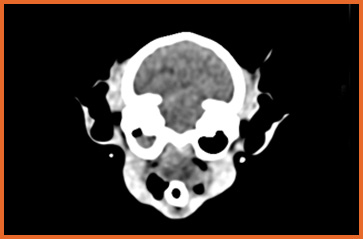

我們提供留院服務並擁有相應的治療設施,亦是小數備有CT電腦掃描及MRI磁力共振等大型醫療儀器的診所及醫院。